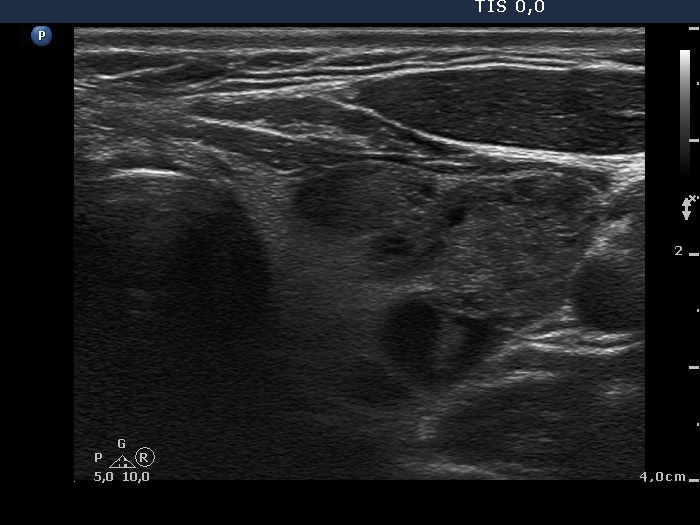

Second examination 3 years later (third row of images)

Ultrasonography. No significant changes could be found. The size of the nodule in the right lobe and that of the multinodular left lobe was unchanged.

Comment. This example emphasizes the importance of the measurement of the volume of the thyroid lobes. The left lobe contained multiple nodules next to each other. Neither of these lesions can be measured correctly. To basis of the follow-up is therefore the volume of the entire lobe and not that of one or another nodule.